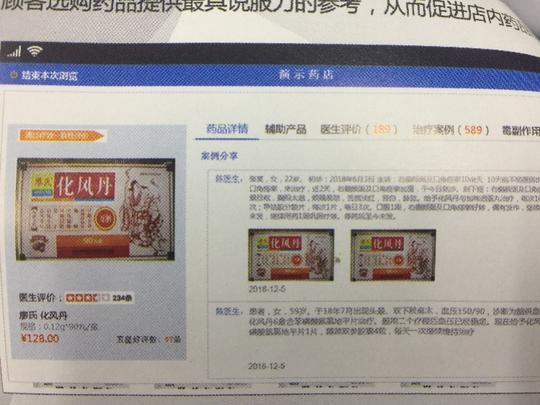

药店可挂名医号,查询医生对药品的评价!这个免费药店系统发布